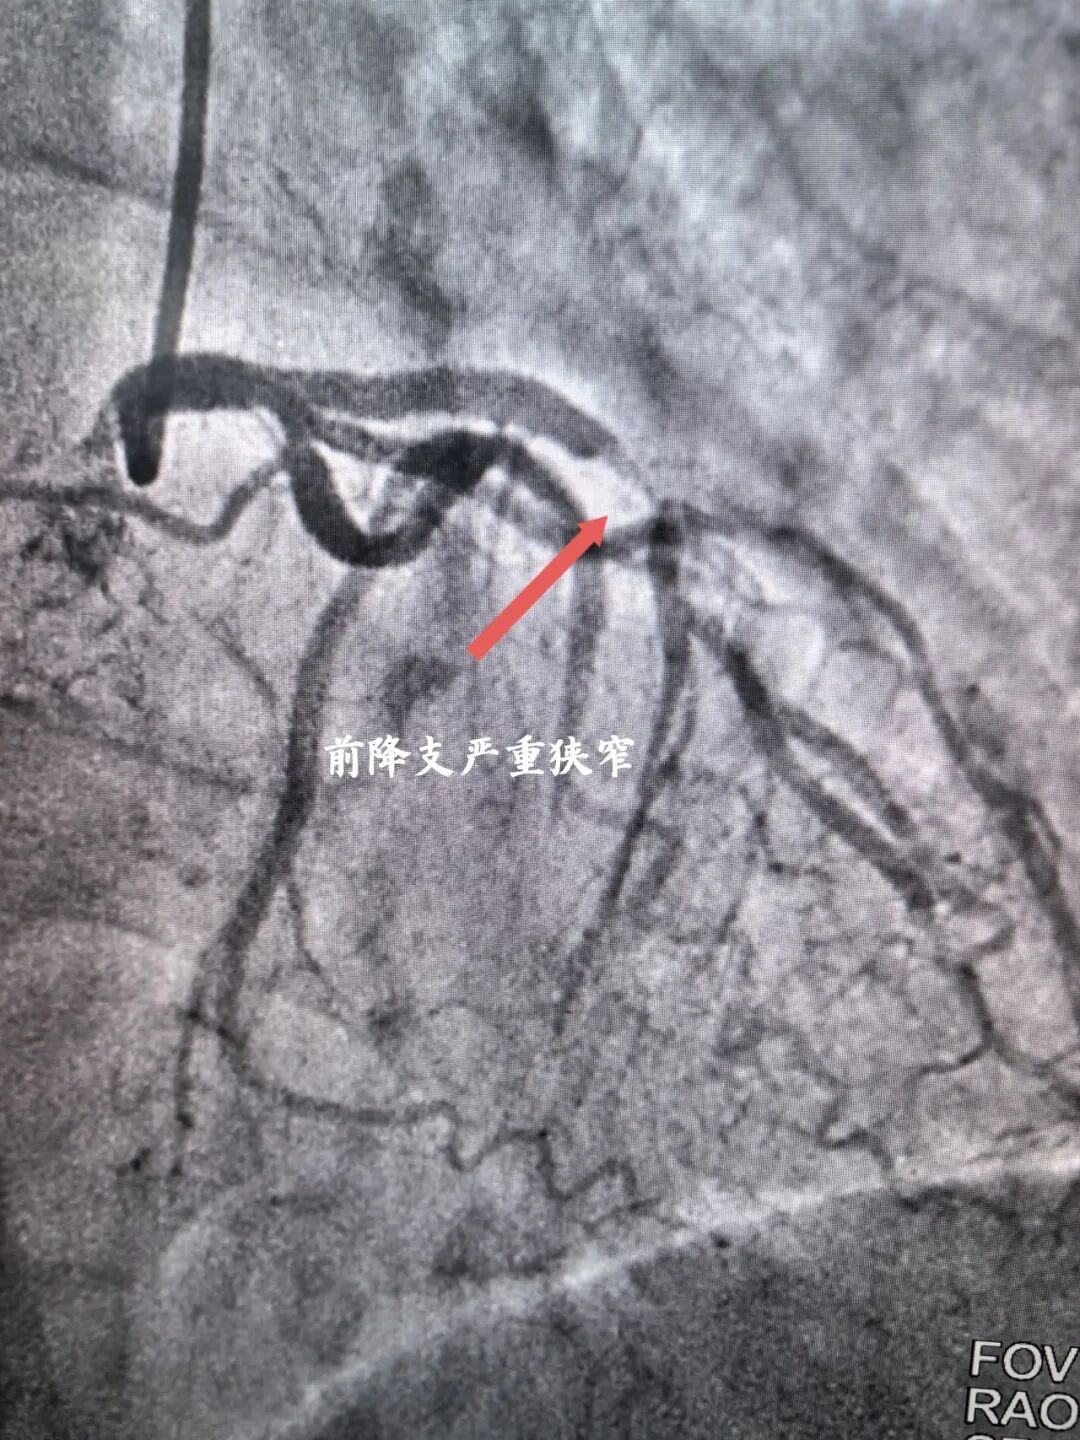

入院完善各项检查后考虑为冠心病合并右锁骨下动脉狭窄可能,经宋坤青主任团队研究后,决定为该患者施行冠脉造影+锁骨下动脉造影。经过严谨的术前讨论及充分的术前准备后,在2024年06月07日上午,宋坤青主任、赵博韬副主任及杨亚楠、冉德聪主治医师为该患者进行了造影手术,结果提示右冠状动脉近近段90%狭窄,前降支近中段90%狭窄,右侧锁骨下动脉闭塞。

前降支严重狭窄